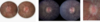

25

Achado?

Sinal de Battle

26

Sinal do Guaxinim